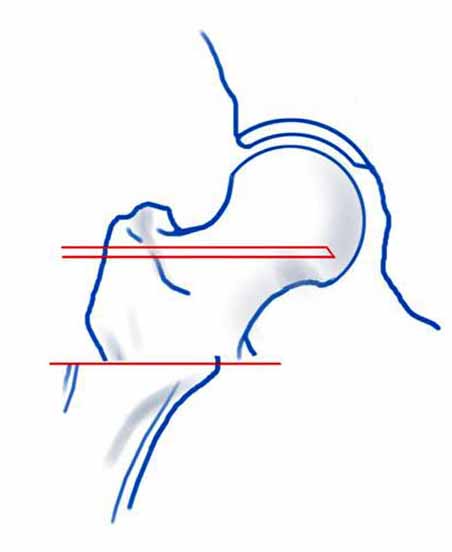

На снимке положение клинка идеальное, но шейка в ротации. Из-за неправильного расчета остеотомии не удалось латерализовать диафиз, и конечность находится в чрезмерном вальгусе. При укорочении с вальгусом увеличивает стресс в зоне между пластинами, и конструкция не выдерживает, и при малой травме может осложниться стрессовым переломом.

Для предупреждения чрезмерного вальгуса во время операции сразу ниже клинка снаружи выше линии остеотомии укладывается костный фрагмент, взятый из остеотомии, который переводит диафиз из медиального положения латерально.

В 120 градусной или в любой реконструкционной клинковой пластине главным является проксимальный, т.е. ближайший к остеотомии винт. Чем ниже остеотомии находится винт, тем больше увеличивается момент рычага, что может привести к несостоятельности (поломке) конструкции. Для вальгусной остеотомии достаточной бывает пластина с двумя отверстиями, но при этом варианте, возможно, длинная пластина пригодится?

Гвоздь подвести под вертел, и оставить проксимальный винт, а остальные шурупы могут быть через один кортекс. Идеально установить "стоппер", который укоротит клинок и латерализует диафиз. Создаст компрессию!